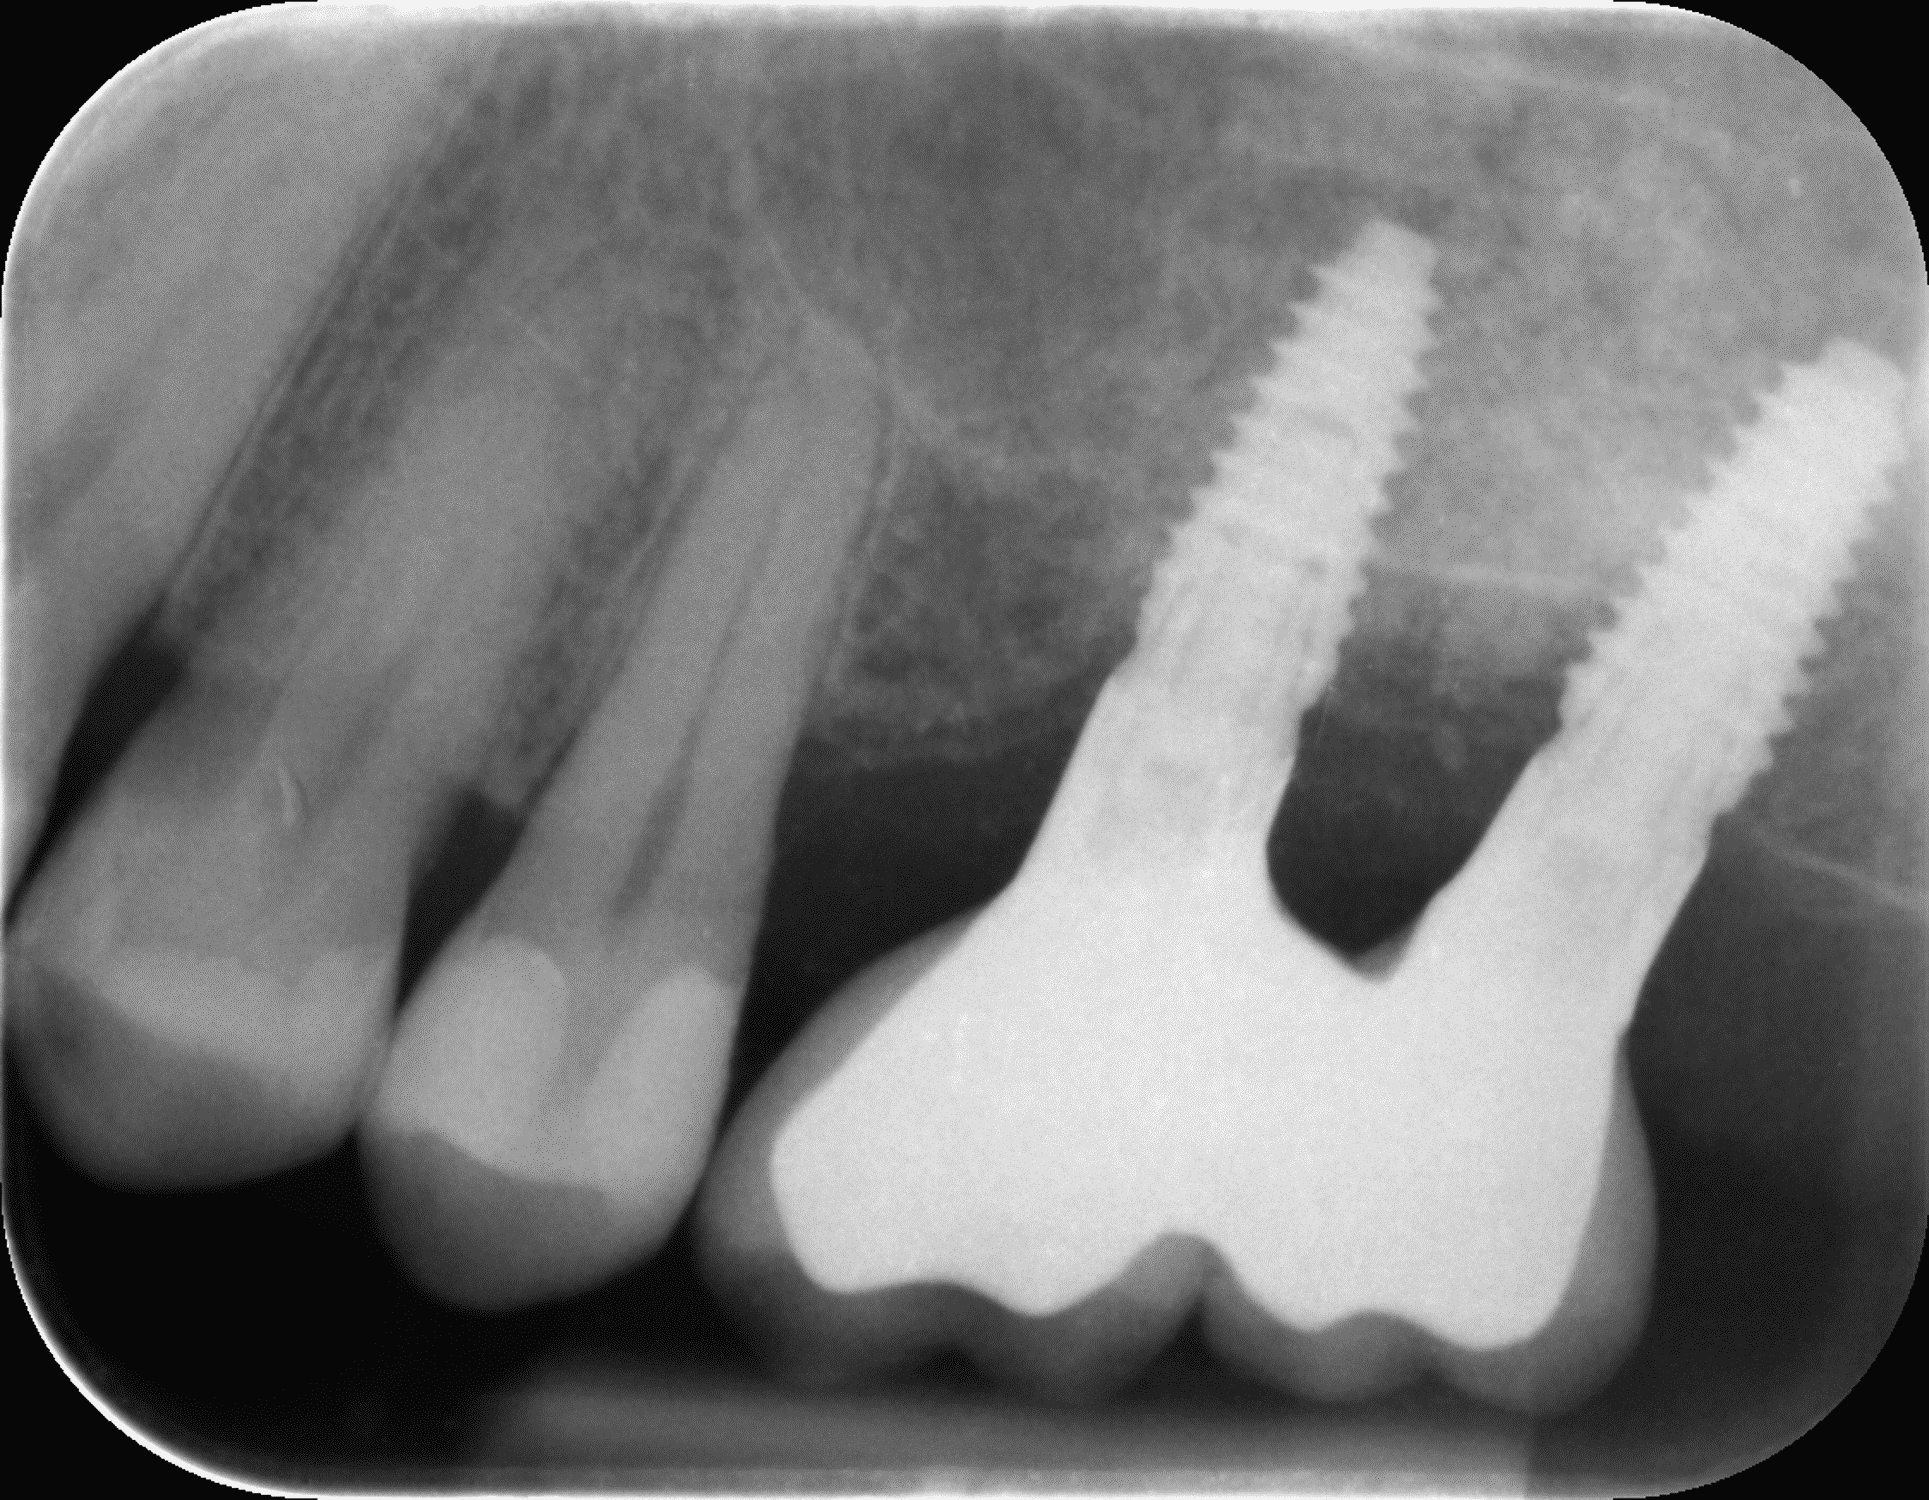

În prima etapă chirurgicală, Dr. Eliza Drăgan a efectuat un lifting de sinus maxilar bilateral.

A doua etapă, inserarea implanturilor, a fost realizată după 6 luni.

Împreună cu pacientul, am optat pentru inserarea implantelor cu ajutorul ghidului chirurgical pentru a plasa implantul în poziția protetică ideală și pentru a permite realizarea coroanelor insurubate pe implant. A fost efectuată scanarea digitală a arcadelor și a ocluziei pacientului, iar împreună cu tehnicianul radiolog de la DigiRay a fost suprapus fișierul .stl al amprentei digitale peste fișierul .dcm de la CBCT, utilizând software-ul 3Shape.

S-a planificat individual poziția și axul de inserție al fiecărui implant.